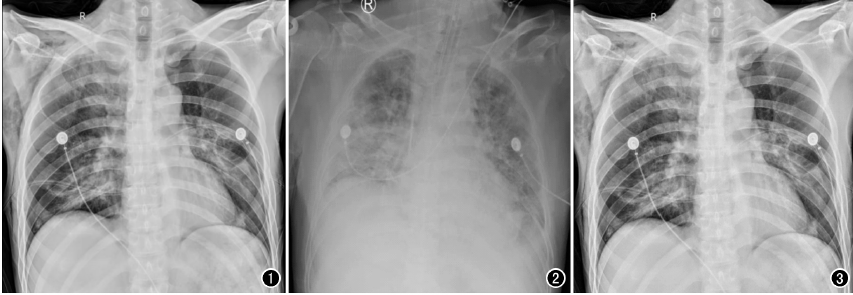

相較于普通DR的百萬攝影像素,近2000萬的高清像素,可以極大的提升床旁檢查效率,包括骨科、新生兒科、心臟外科、重癥監護科、急診科等患者的快速檢查。相較于目前市面上的低像素移動DR設備,100微米平板移動DR,在圖像的分辨率、寬容度上都全面優于常規的130微米左右的移動DR設備。

以心臟手術為例,開胸心臟手術多數是在低溫、全麻和體外循環下進行,胸腔創傷較大、風險極高,心臟術后,心外科醫師為了能及時了解術后患者的雙肺復張情況、氣管插管導管頭端位置以及手術并發癥等情況,需要及時對患者進行胸部X線片檢查,以便觀察氣管插管位置,一般來說,插管位置下端應位于第3胸椎水平,過深或者過淺都將影響呼吸機的輔助效果,應確保位置準確,以免影響通氣狀況。另外,包括對于相關手術并發癥的檢查,包括:胸腔積液、氣胸、肺不張等常見問題,需要及時進行胸部X光檢查。相較于幾百萬像素的移動DR,百微移動DR,在圖像質量上顯示更清晰,檢查效率更高,更利于醫生及時進行處置。